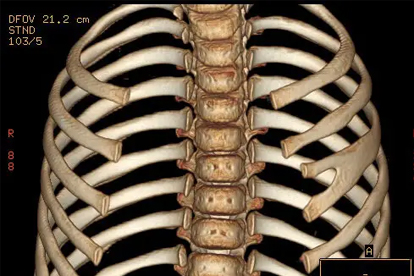

3、肋软骨炎

肋软骨与胸骨连接处发生无菌性炎症时,会出现局部压痛和肿胀感,疼痛可放射至肋骨下缘。急性期可冷敷减轻肿胀,慢性期改用热敷,遵医嘱使用布洛芬缓释胶囊、塞来昔布胶囊或氟比洛芬凝胶贴膏。睡眠时避免压迫患侧,减少上肢负重活动。